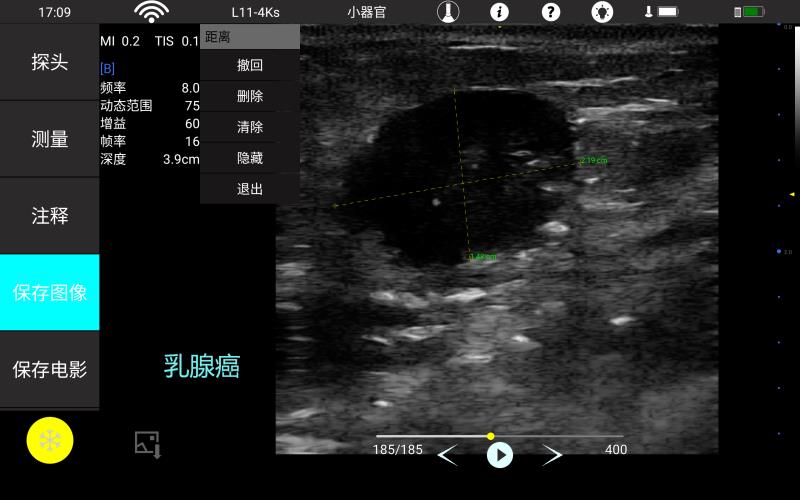

多种专科软件包,含常规测量,腹部,产科,

妇科 心脏,小器官,神经应用软件包,使检查更便捷。